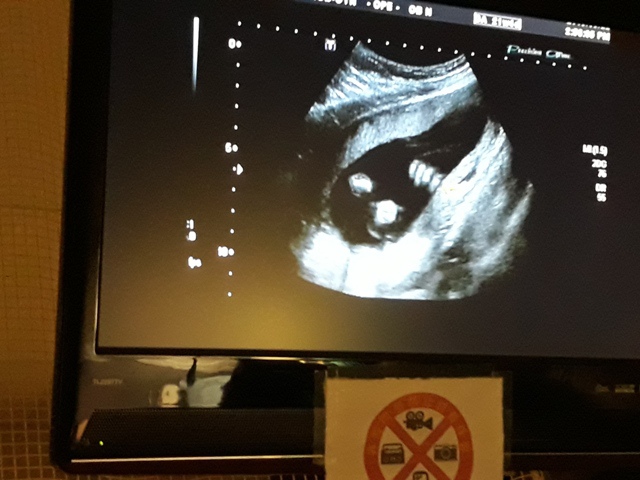

當小純進入診間看診時,我並沒有進去,因為小純說,有時男生不能進去,會被請出來。在外頭等待的我感到很緊張,不久之後,謢理人員請我進入診間,我嚇了一跳,想說發生什麼事了,進入之後,得知小純真的懷孕了,而且已懷了九星期又五天。看診的醫師說,驗孕棒第二條線淡淡的,沒想到胚胎照出來那麼大了,說Baby很健康。還說一閃一閃的是他的心跳,有頭、有手、有腳還有臍帶。小純後來說看了內心覺得很感動,才叫我一起進去看。

小純肚子裡的Baby超音波圖↓

進到超音波室後,發現幫小純照超音波的就是關醫師(小純原本以為會是超音波技術員,照完才會有醫師來,結果是關醫師從頭照到尾)。關醫師一項一項的幫小飛做檢查,雖然是高層次的超音波,比平常的產檢還仔細,但是很多東西我和小純都看不太出來,但是手、腳的指頭和脊椎都很清楚。

檢查到外生殖器時,關醫師說『平平的』是女生,我和小純聽了都感到很訝異,上一次的產檢,關醫師不是說看到『凸凸的』是個男生,月中羊膜穿刺的報告出來之後,小純也有詢問打電話給他的人,也說是男生,怎麼性別翻盤了,小純跟關醫師說,羊膜穿刺的報告說是男的,關醫師說,既然羊膜穿刺的報告是男的,那就是男的沒錯,以羊膜穿刺的報告為準,超音波也有可能會因為角度的問題而誤判,後來關醫師照到小飛把腳打開的樣子,確定是男的。